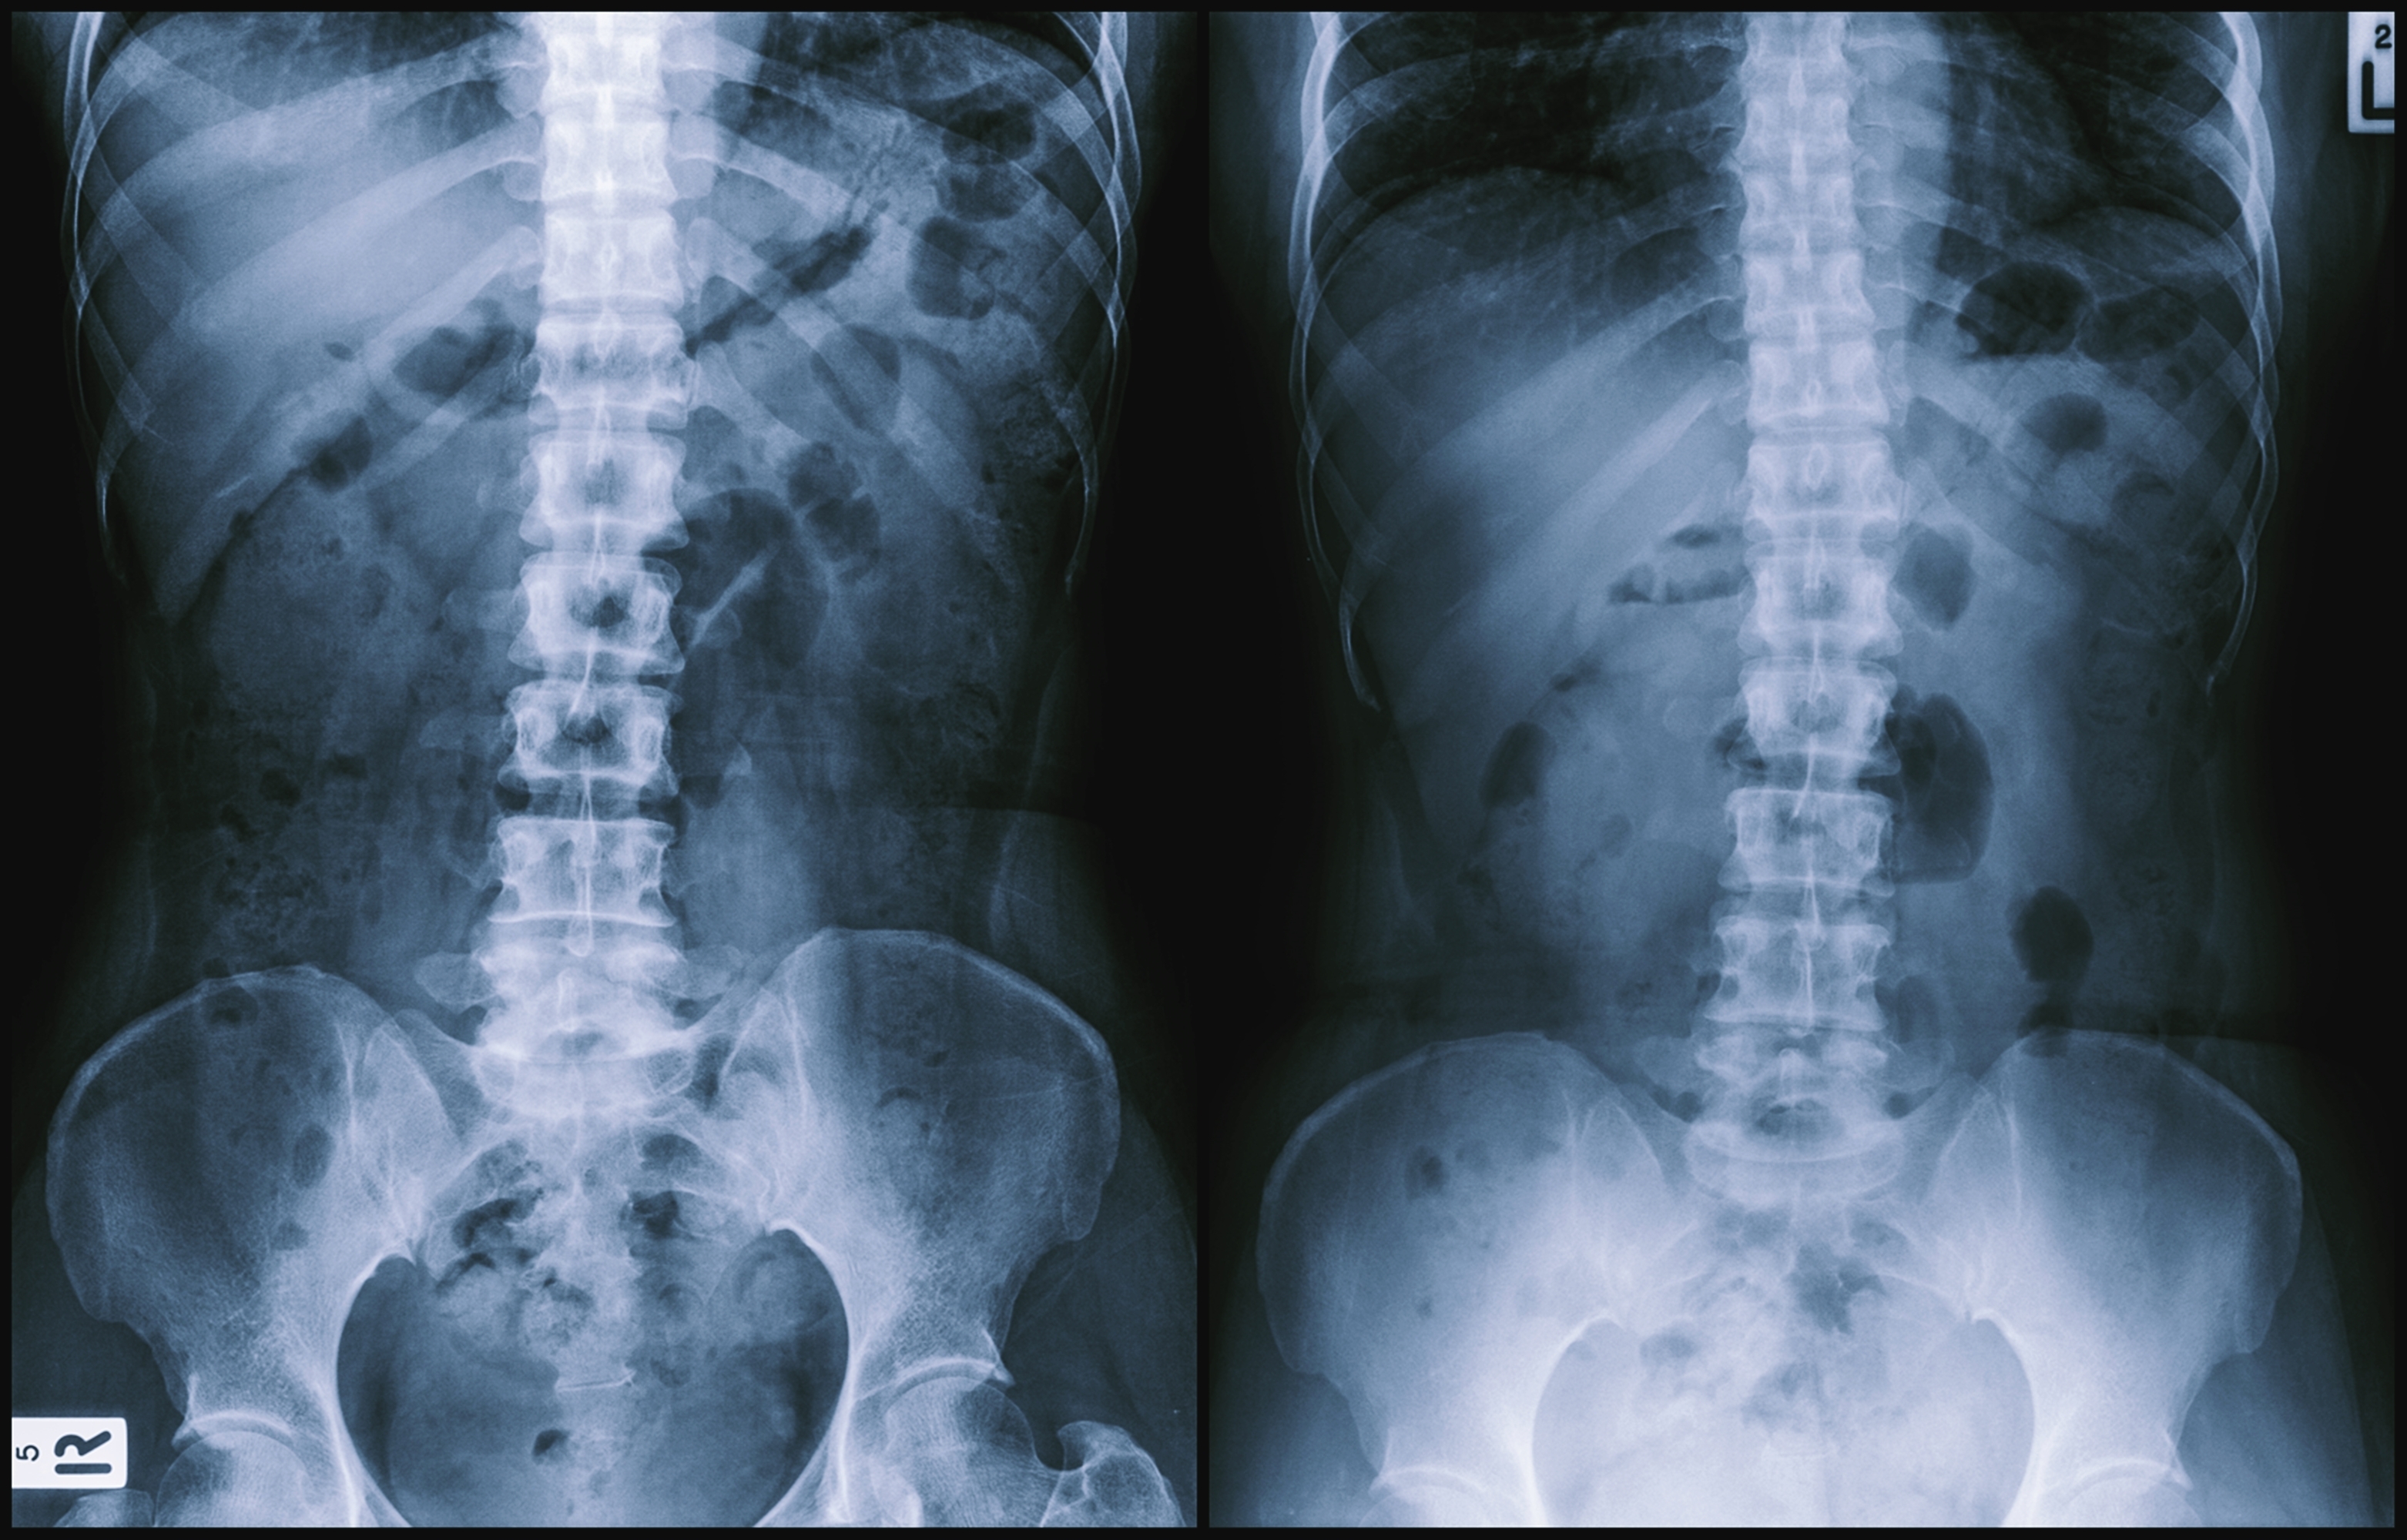

복부 X-ray는 촬영 시 숨을 내쉬고 참습니다. 참는 것은 motion artifact를 줄이기 위함인데 왜 하필 내쉬고 참을까요?

흉부와 복부를 구분 짓는 구조물은 무엇일까요? 횡격막(diaphragm)입니다. 숨을 들이쉬면 횡격막이 아래로 이동하고, 내쉬면 위로 올라옵니다. 숨을 들이쉬면 횡격막이 복부를 위에서 누르게 됩니다. 아무래도 장을 비롯한 복부 장기들이 눌릴 수 있고, 눌린 장기를 평가하는 것은 제한이 있습니다. 숨을 내쉬고 외력이 없는 상태의 복부 장기를 평가 해야 정확한 병변 판단이 가능합니다.

특히 복부 X-ray에서는 간, 췌장, 비장, 신장 등과 같은 고형 장기 (solid organ)보다는 장내 공기 (bowel gas)를 평가하는데 이점이 있기 때문에, 압력이 없는 상태의 장내 공기 패턴을 평가하는 것이 중요합니다.

정상 복부 X-ray. 장내 가스는 검게 보인다.